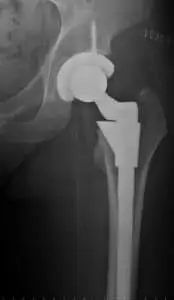

Hip replacement surgery is one of the most common and successful orthopedic procedures performed today. While most patients recover well, a significant number experience persistent pain, stiffness, or limited mobility long after the joint has healed. This lingering discomfort is often related to scar tissue formation, fascial adhesions, and neuromuscular dysfunction—factors that may not respond well to conventional physical therapy alone.

Studies estimate that 7–28% of patients experience persistent or unexplained pain after total hip arthroplasty (THA).¹ This pain may not originate from the prosthesis itself but from soft tissue imbalances, including tension in the gluteal, iliopsoas, piriformis, and tensor fascia latae muscles.